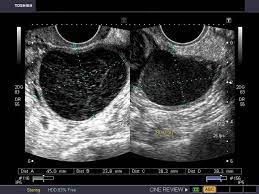

Ovarian Cyst Pelvic Ultrasound Female / Benign And Malignant Tumours Of The Female Reproductive System Undergraduate Diagnostic Imaging Fundamentals / A pelvic ultrasound allows quick visualization of the female pelvic organs and structures including the uterus, cervix, vagina, fallopian tubes and ovaries.. The most common indications for imaging of the pelvis in girls include ambiguous genitalia, prepubertal bleeding, primary amenorrhea, pelvic mass, and pelvic pain. A 51 year old, gravida 3 para 2, comes to the office because a routine health maintenance examination. These are called simple ovarian cysts. Pelvic ultrasound shows a simple right ovarian cyst measuring 4 cm in diameter. Her last menstrual period was at age 49.

Ovarian cysts, also known as ovarian masses or adnexal masses, are frequently found incidentally in asymptomatic women. Ultrasound imaging of the pelvic area is used to help determine the cause of symptoms such as pelvic pain and abnormal bleeding in women. She has no specific complaints at this visit. This is called a tubal pregnancy. The left ovary is mostly displaced by a large 7.5cm ovarian cyst.

These scans often also find cysts in the ovaries. It is the single most effective way of imaging and characterizing ovarian cysts. Follicle production is normal in all premenopausal women. It is excellent at this task as the ovaries naturally contain fluid called follicles or cysts. Eggs (ova), which develop and mature in the ovaries, are released in monthly cycles during the childbearing years. The left ovary is mostly displaced by a large 7.5cm ovarian cyst. There were no ovarian cancers found. Most of the time those extra exams are not needed.

Ultrasound uterine wt 0.16 0.80 < 0.001 ≥ 200 g patient wt 0.09 0.73. Pelvic ultrasound shows a simple right ovarian cyst measuring 4 cm in diameter. A retrospective review of an entire clinical series of 152 women over 50 years of age, in whom cystic lesions without solid parts had been diagnosed by ultrasound, found there were no malignancies in 58 completely anechoic lesions less than 5 cm in diameter. Ovarian cysts in teenagers are fairly common and typically don't cause further issues. These are called simple ovarian cysts.

The right ovary measures up to 3.4cm and has a normal ultrasound appearance.

Most cysts are harmless, but some may cause problems such as rupturing, bleeding, or pain; A cyst on your ovary can be found during a pelvic exam. If your healthcare provider finds an unexpected cyst or enlarged ovary during a pelvic exam, you should have a vaginal ultrasound to assess for cancer. Another type of cyst happens when fluid accumulates in the follicle. See if a fertilized egg is growing outside the uterus. The left ovary is mostly displaced by a large 7.5cm ovarian cyst. Followup of ovarian cysts in premenopausal women •simple cysts •1.<3cm=normal finding •2. Check for growths or masses like ovarian cysts or uterine fibroids. Because of concerns about ovarian cancer, these cysts may be followed with repeated imaging over many years. Find the cause of urinary problems. Ovarian cysts in teenagers are fairly common and typically don't cause further issues. A pelvic ultrasound allows quick visualization of the female pelvic organs and structures including the uterus, cervix, vagina, fallopian tubes and ovaries. What are ovarian cysts & pelvic masses ovarian cysts are a common occurrence in countless women and often resolve on their own.